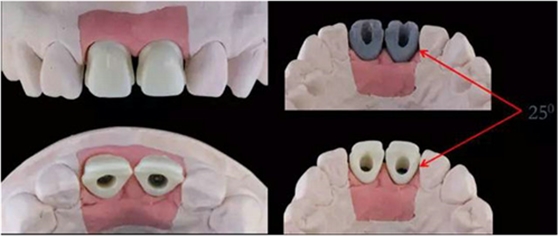

11,21 ASC 全瓷基臺(tái)一體冠蠟型

Asc基臺(tái)數(shù)字化設(shè)計(jì)

螺絲通道改變25°

通過(guò)改變螺絲通道角度,調(diào)整螺絲開(kāi)口位置